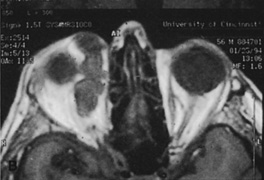

Figure 10. A. Large, well-encapsulated intraconal mass on MR scan. B. Small lateral canthotomy incision will be used to perform lateral orbitotomy and remove the intraconal mass.

Fig. 11. A. Lateral canthotomy incision is made with straight iris scissors. B. Periosteum is elevated off of the lateral orbital rim. C. Wide undermining allows retraction of the skin incision to permit superior and inferior osteotomies to be made with the air-driven saw. D. The bony rim has been outfractured. Because of the distensibility of the skin, it is possible to remove a large bone flap through the small canthotomy incision. E. The intraconal mass is extracted with the aid of the cryoprobe. F. The bone fragment is positioned for resuturing.